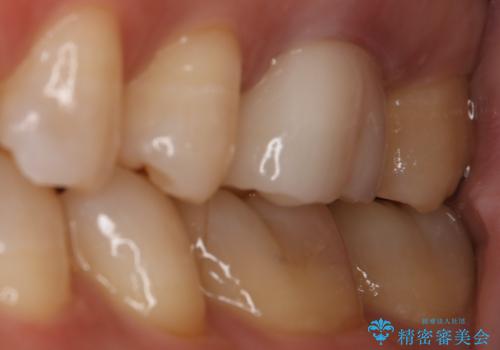

銀歯を白くしたい セラミックインレー

- 左上7番の銀歯をセラミックにやり変え希望の患者様です。

切削量・形態からセラミックインレーでの治療を計画しました。

銀歯とその直下のう蝕を除去した後、CRにて裏層しています。

インレー装着の際はラバーダムを使用しています。